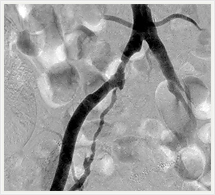

画像紹介(四肢血管治療編)

経皮的血管形成術(PTA)は先端に小さく折りたたまれたバルーンを装着したカテーテルを用いて、狭窄または閉塞してしまった血管を拡張することにより、血液の流れを確保、再開させる手技です。

この治療ではバルーンカテーテルに加えてステント(金属製のチューブ)を留置することもあります。